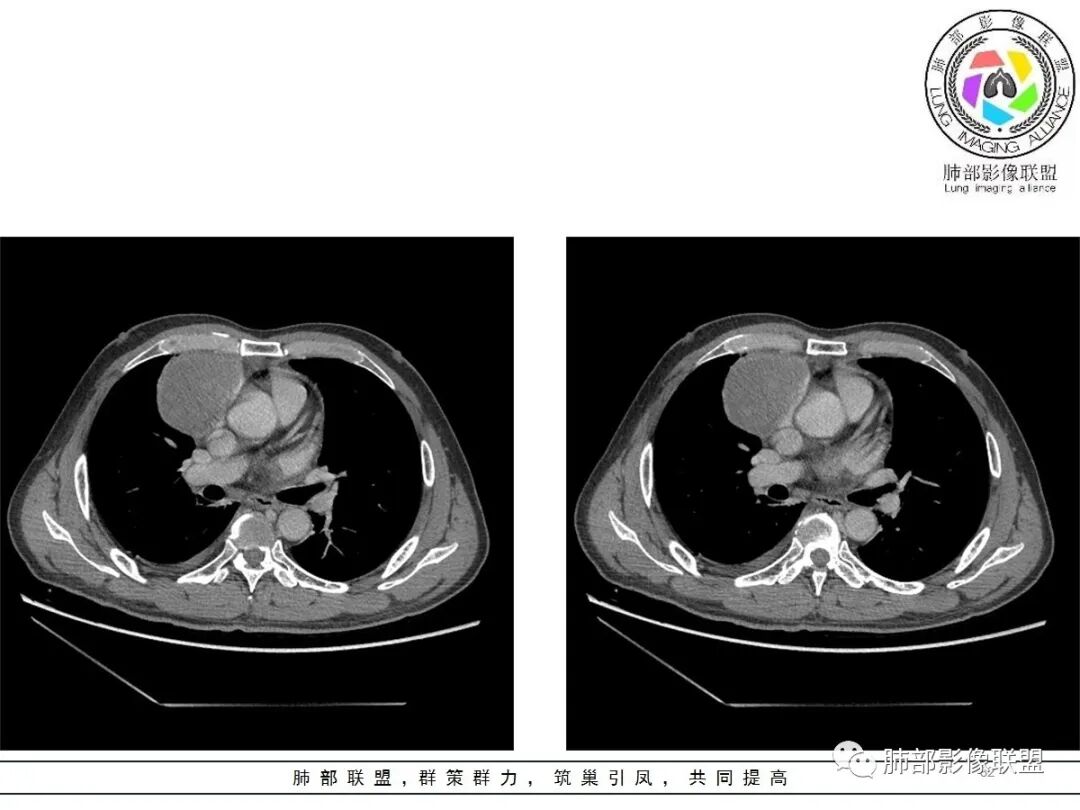

大雄:老年男性  急性起病 胸痛1天前纵隔占位伴右侧少量胸水,肿块整体膨隆,密度不均匀,可见坏死,纵隔脂肪间隙模糊不清常规考虑胸腺瘤/癌并梗死

一切∮随缘:定位肺外,病变位于右前纵隔,与肺部交接面清晰,有胸膜尾征,心包局部受压,部分包绕主动脉血管,平扫密度均匀,形态规则,膨胀性生长,增强扫描壁有强化,内容物无明显强化,考虑1:淋巴瘤2:胸腺瘤3:神经鞘瘤4:支气管囊肿

亚东:前纵隔囊实性肿物,形态尚规则 ,与心包分界不清,内可见小气泡,嚢内平扫密度低,强化不明显,囊壁强化,右胸腔积液,淋巴结肿大不明显,化验白细胞高,支持囊肿伴感染。

小强:前纵隔肿块,边缘模糊,其内有点状气体影,环形强化(肉芽肿?),心包胸膜受累,疾病谱:胸腺瘤(一般是侵袭性胸腺瘤累计心包,胸膜,强化不符合)淋巴瘤,生殖细胞瘤(年龄,AFP不高不负),考虑畸胎瘤,囊性畸胎瘤合并感染,边缘模糊,累计心包胸膜,3.19病变进展,胸腔积液,可能有破溃

采莲:老年男性,胸疼病史,右上前纵隔肿块,边缘光滑,平扫内部密度稍均匀,轻度强化,内有低密度区,与支气管关系不大,右侧少量积液。考虑来源纵隔,老年男性,胸腺瘤或胸腺癌,鉴别淋巴瘤。

冥冥之中:定位,右前纵隔

定性,肿块边缘模糊,右侧胸腔积液,上腔静脉边缘侵袭,恶性

年龄68常规考虑胸腺癌,但是里面有脂肪成分,周边有钙化,畸胎瘤不能排除

综合考虑,前纵隔恶性病变,畸胎瘤>胸腺癌

廖鹏飞:可疑胸腺动脉进入肿块

廖鹏飞:考虑胸腺瘤合并感染,畸胎瘤待排

修*:前纵隔偏右侧肿物,点状钙化,轻度强化,伴胸腔积液,考虑胸腺瘤B2型。

岁月:男性,68岁,右胸痛一天,无家族史,右上中叶纵膈旁占位;抽烟50年,3天1包。wbc高。与纵膈脂肪间隙不清,胸水,快进快出 分叶,有血管样强化,9.1-11.4-10.9。诊断:错构瘤,似乎都符合;但如果恶性放在前面,肉瘤、恶性。鉴别:错构瘤、侵袭性胸腺瘤;处理:经皮肺活检、手术。

王秀仙:右侧前纵膈肿块,密度不均,局部边缘可见点状钙化,其内可见点状低密度,与纵膈血管间脂肪间隙消失模糊,右侧胸腔积液,考虑纵膈畸胎瘤或皮样囊肿破裂。鉴别胸腺鳞癌。

必有路:老年人,右前纵隔占位,发病前纵隔脂肪干净,突发起病伴胸痛,白细胞增高病灶整体密度较为均匀,内有点状脂肪密度,位置个人觉得理胸腺区有点偏下,大部分囊性为主1、胸腺瘤伴突发梗死  突发起病,老年男,不支持点,位置偏下,囊变坏死太彻底,右侧胸廓内动脉没有增粗(实性肿瘤,往往会有间接供血增粗)倾向支持囊性病灶合并破溃感染2、囊性畸胎瘤伴破溃  影像上可以支持,脂肪含量比较少,发病年龄不太支持3、 皮样囊肿 可以有脂肪密度4、 支气管囊肿 理论上胸廓内都可以发生,肺内 后纵隔多见 张力大 圆5、心包囊肿  中纵隔更为多见综上,皮样囊肿>囊性畸胎瘤>胸腺瘤

肿瘤样病变破裂所致纵隔炎应该没错

南边:肿瘤或肿瘤样病变破裂所致纵隔炎,这是大方向

结果:符合B型胸腺瘤伴出血,坏死囊性变,局部脓肿形成